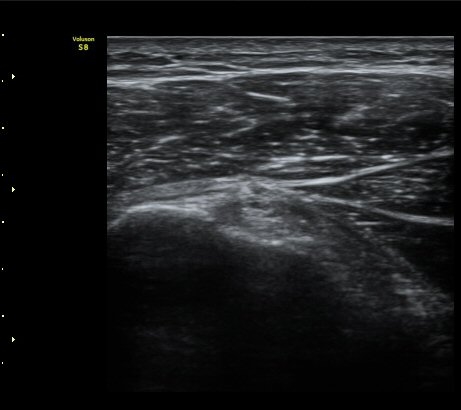

ÀÌµÎ¹Ú±Ù°Ç È¾´Ü¸é°Ë»ç¿¡¼­ ƯÀÌ ¼Ò°ßÀ» º¸ÀÌÁö ¾ÊÀ½(»çÁø 1, 2).